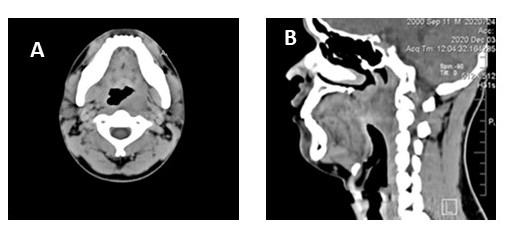

Paciente sin antecedentes médicos ni de radiación previa, niega hábitos tabáquicos y etílicos. Dentro de los antecedentes familiares, hermana con leucemia. Al examen físico de ingreso en nuestra institución, Karnofsky 100 %, cabeza y cuello: cuello simétrico, con movilidad conservada, sin lesiones en piel, tiroides no visible ni palpable; cavidad oral: sin trismo, mucosa oral sin lesiones, lengua móvil, a nivel de orofaringe en pared posterolateral izquierda se visualiza lesión exofítica, no ulcerada, no se palpan adenomegalias cervicales. Nasofibrofaringolaringoscopia: se observa lesión exofítica que protruye a nasofaringe, originada en pared posterior de orofaringe, sin ulceración, con presencia de vascularización en su superficie, cuerdas vocales sin lesión funcional ni orgánica, senos piriformes libres (Figura 2). Resto del examen físico sin alteraciones aparentes.

Dentro de los estudios de imagen presenta tomografía de cuello con contraste endovenoso en la cual se aprecia imagen hipodensa difusa que compromete la pared lateral izquierda de orofaringe con un diámetro de 4,28 cm x 2,83 cm, que disminuye la luz de la orofaringe y con realce heterogéneo luego de la administración del contraste, sin ganglios patológicas (Figura 3). En RMN de cuello se evidencia lesión sólida, en pared posterior de orofaringe con obliteración de la luz, de 4,3 cm x 3,71 cm, infiltrando fascia prevertebral y músculos prevertebrales adyacente a cuerpo vertebral de C2 (Figura 4). Estudios de extensión pulmonar y hepático sin lesiones sugestivas de metástasis.